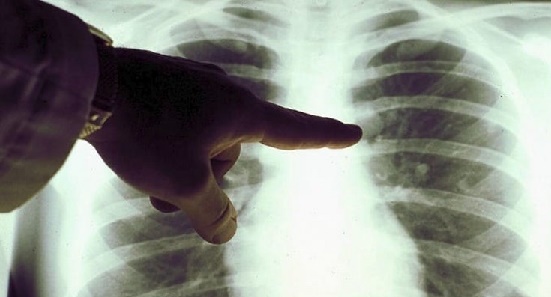

Il tumore al polmone si colloca come la terza neoplasia più diagnosticata in Italia, superata solo dal cancro alla mammella e da quello del colon-retto. Secondo un rapporto del 2024, circa 45.000 persone vengono colpite ogni anno nel Paese. La malattia risulta essere due volte più comune negli uomini rispetto alle donne e si conferma come la principale causa di decessi oncologici. Tuttavia, i dati recenti mostrano un significativo abbattimento della mortalità, con una riduzione del 46,4% tra le donne e del 35,5% tra gli uomini sotto i 50 anni. Questi risultati sono incoraggianti, considerando che il tumore ai polmoni rappresenta la prima causa di morte per cancro negli uomini giovani e la seconda nelle donne, dopo il cancro della mammella. I progressi nelle terapie hanno contribuito a migliorare le prospettive di sopravvivenza dopo la diagnosi di carcinoma polmonare.

L’aspettativa di vita post-diagnosi varia in base allo stadio della malattia e al tipo specifico di tumore. In generale, la sopravvivenza a cinque anni per il tumore del polmone è del 16% per gli uomini e del 23% per le donne in Italia. Le possibilità di sopravvivenza aumentano notevolmente negli stadi iniziali, con oltre il 70% di sopravvivenza a cinque anni per i pazienti diagnosticati in stadio I.

La campagna “Illumina Novembre” si propone di trasmettere messaggi cruciali per la prevenzione e la cura del tumore al polmone. Uno dei punti fondamentali è la necessità di una diagnosi precoce, che consente di intervenire con trattamenti meno invasivi e con maggiori probabilità di guarigione. Si invita la popolazione a consultare il medico di medicina generale per valutare l’opportunità di sottoporsi a una tomografia computerizzata (TC) a basso dosaggio del torace, soprattutto per coloro che presentano sintomi sospetti o appartengono a gruppi a rischio.